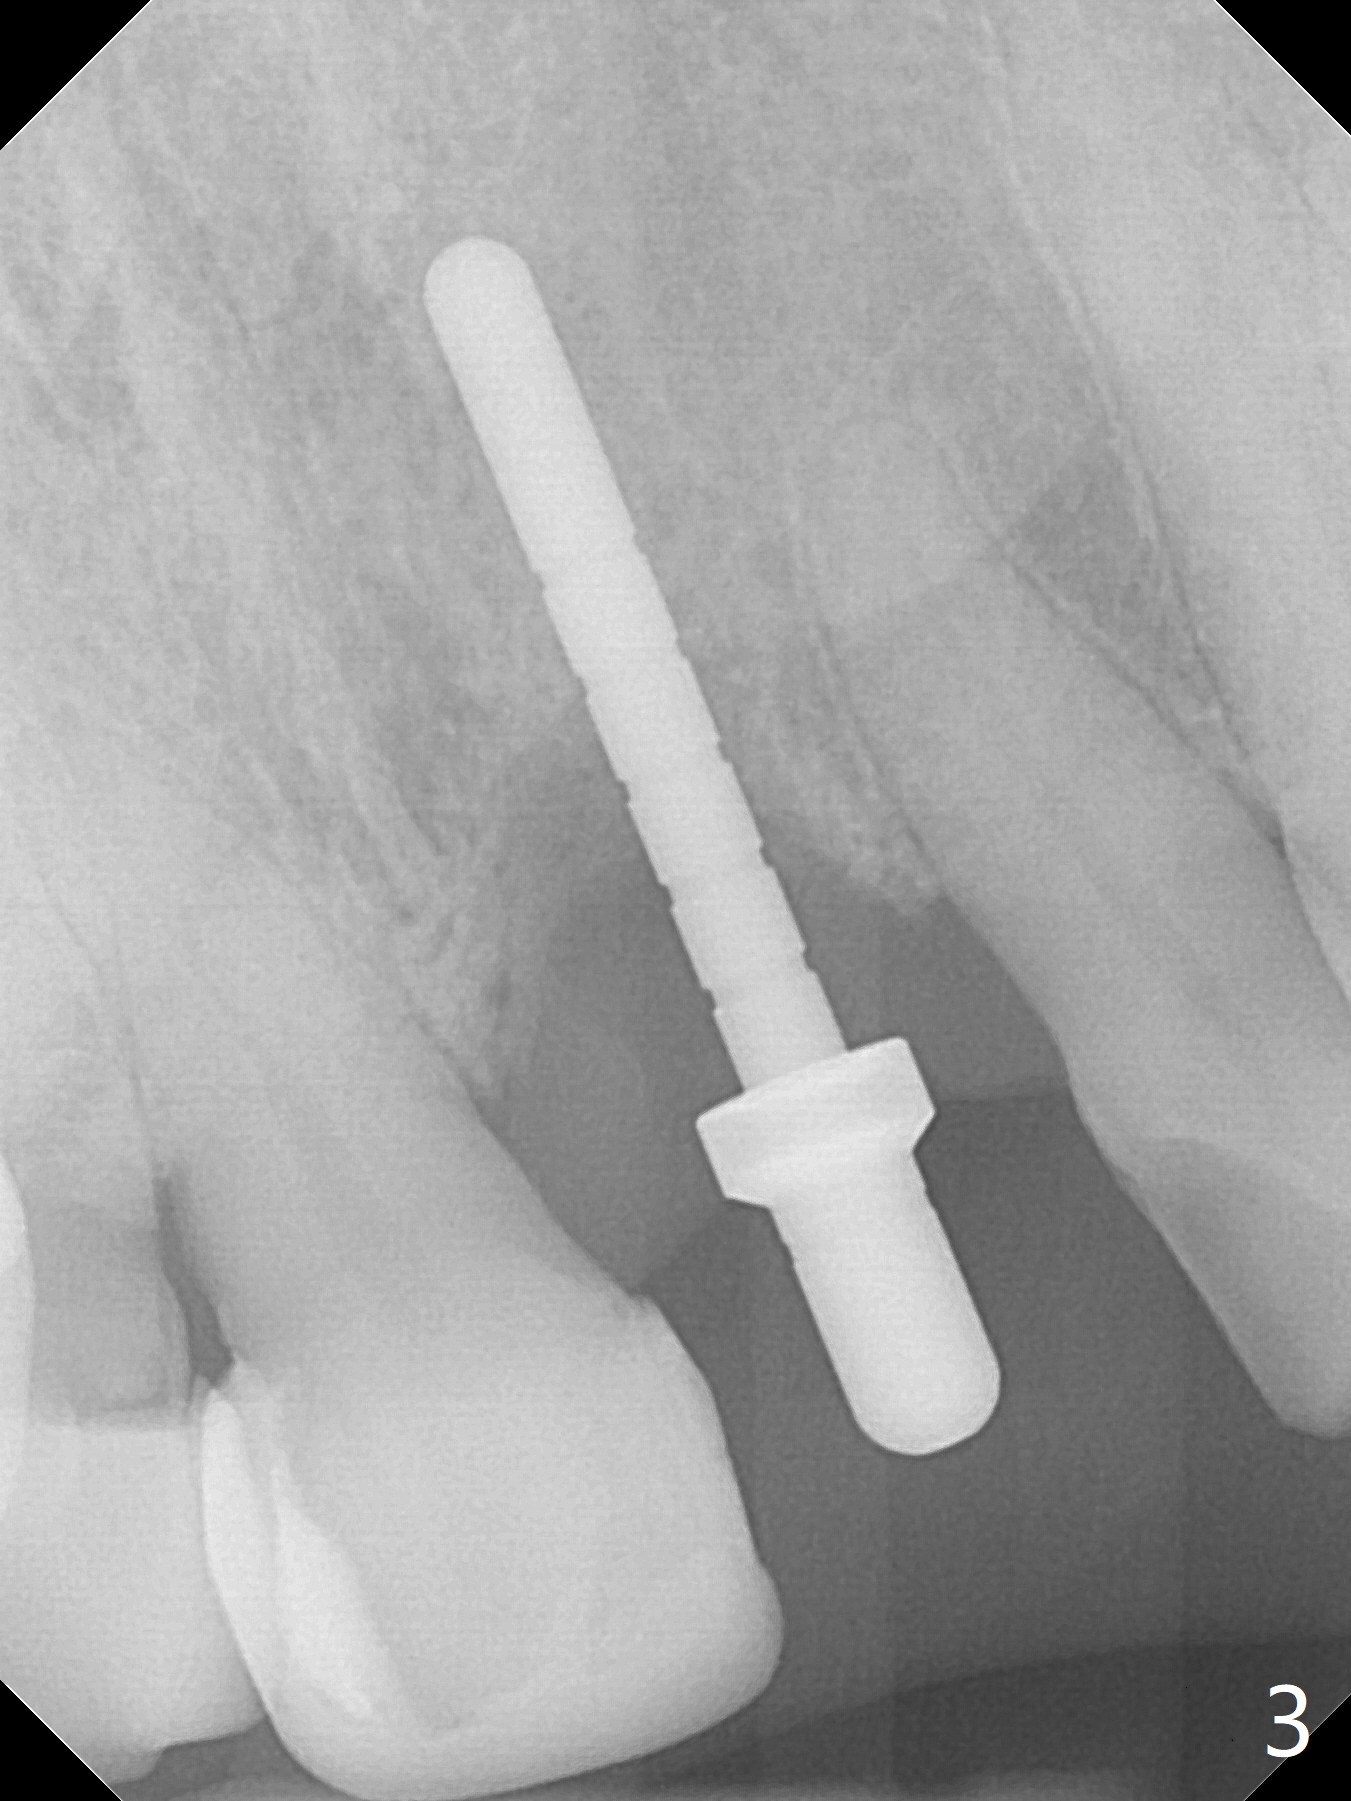

In spite of the incisobuccal shift of the tooth #9 with gingival recession (Fig.1) and loss of the buccal plate (intraop finding), there is no buccal contour collapse (Fig.2 *), due to the presence of the buccal bone of the neighboring teeth and the root of the affected tooth. After extraction, osteotomy (Fig.3) and dummy implant try in (Fig.4), a definitive implant is placed palatally with the buccal gap (Fig.5 *). In fact there is mild buccal contour collapse prior to bone graft (Fig.5 arrow). When allograft (Vera, Fig.6,7 *) is packed buccal to the implant and overlying abutment as a solid support, the buccal contour seemingly returns normal (Fig.6 arrowhead). An immediate provisional is fabricated to prevent loss of the bone graft during healing period. Bone graft kept in place by the provisional turns yellow 6 days postop (Fig.8). The buccal plate remains strong, while the fistula becomes indistinguishable. After adjustment of the provisional margin a few times (nearly 3 months postop, Fig.9,10), the gingival margin appears to have grown incisally, as compared to Fig.1. There is minimal buccal bone collapse (Fig.10). Dislodgement of the abutment and provisional forces her to return 1 year 4 months postop; the socket has healed (Fig.11). The buccal plate is not concave 1 year 4 months postop (Fig.12). The gingiva is slightly recessive (Fig.13) with mild buccal plate concavity (Fig.14) immediately before cementation. The implant could be placed ~ 1 mm deeper (Fig.15).